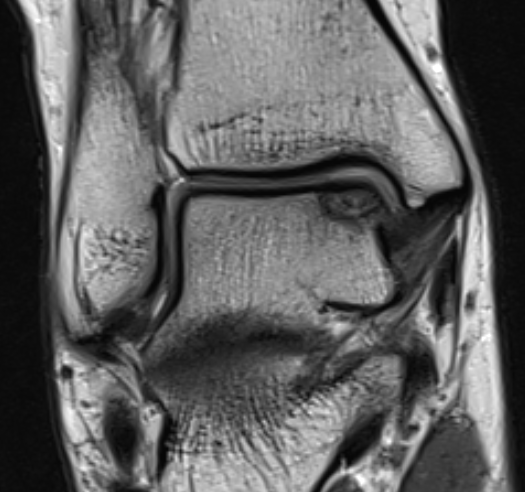

MRI

Stable lesion (Stage I) - cartilage intact, no synovial fluid under lesion

Unstable lesions (Stage II or III) - cartilage breach, synovial fluid under lesion

Displaced lesion with resultant osteochondral defect

Stable lesion with intact cartilage and no synovial fluid under lesion

Stage III completely detached but not displaced